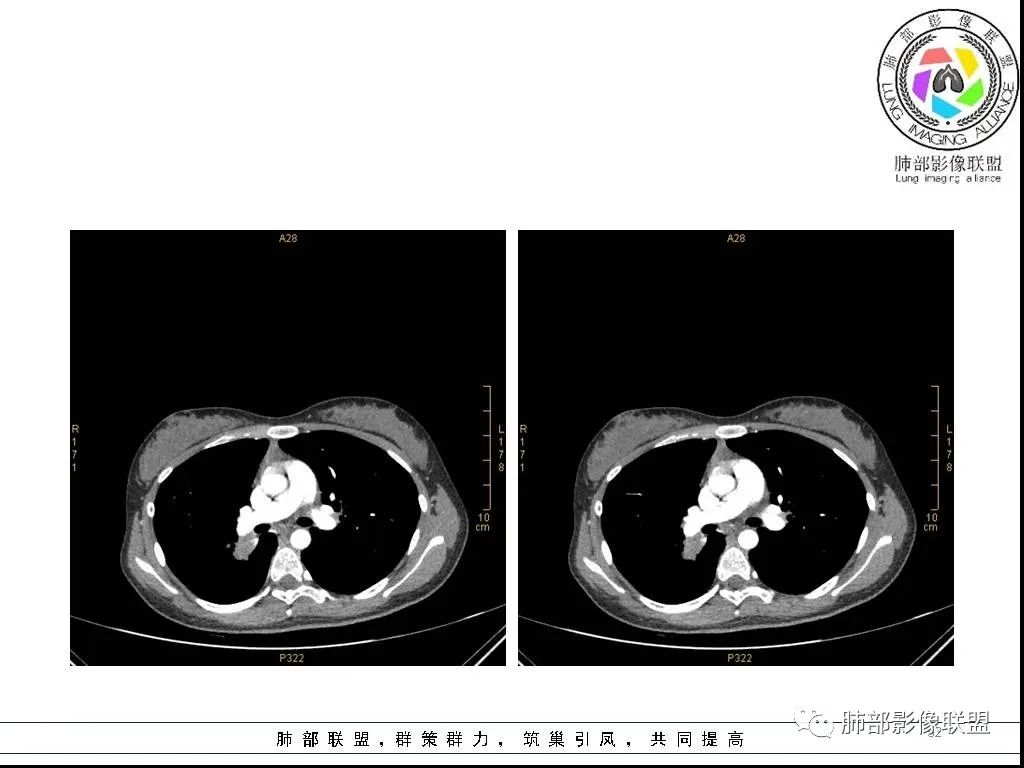

右肺炎症性病变1例CT影像讨论

年轻女性,病程长,咳嗽少痰4个月,辅检未见特殊,CT:右肺团块影,跨叶,主体在下叶背段,外大内小,边缘以膨隆为主,部分平直内收,深分叶,周围有模糊晕,可疑卫星灶,胸膜增厚,糊墙,支气管近端部分进入,粘液栓,有坏死空腔,内壁光整,部分血管侵蚀,强化不均,延迟,明显;同侧R10、7、R4淋巴结肿大,考虑肉芽肿炎,结核,需要与肿瘤鉴别:16岁,女性,诊断肿瘤需要勇气,跨叶多见于炎性,需要进一步活检。

16岁女性,咳嗽,咳痰4月,无发热,白细胞不高,炎性指标(CRP,PPT)不高,血沉增高(75mm/h)。影像表现:右肺胸膜下不规则肿块影,边缘平直,U型凹陷,桃尖征为主,纵隔窗部分层面似有多个结节融合感,近端支气管扩张,堵塞,局部呈鬼脸样改变。边缘可见长短不一毛刺影,周围见晕征,远端见多个小结节卫星灶。胸膜大面积反应性增厚,增强后不均匀中度渐进性强化,局部干酪样坏死可能(CT值-32~-15)内部血管走行较正常,破坏不明显。 医学百科网 | YxBaike.Com

综合分析:病灶边缘平直,U型凹陷,桃尖征为主,周围见晕征,远端见多个小结节卫星灶。胸膜大面积反应性增厚,增强后不均匀中度渐进性强化,加上临床的表现,大方向支持炎性肉芽肿。疾病谱:隐球菌,结核,普通感染,OP,淋巴瘤。结合临床与影像表现:初步诊断:隐球菌可能,诊断依据:一是临床症状及检验指标支持,二是胸膜下肿块,边缘平直,U型凹陷,桃尖征为主,周围见晕征,远端见多个小结节卫星灶,胸膜大面积反应性增厚,增强后不均匀中度渐进性强化,局部干酪样坏死,鬼脸征,血管走行较正常,有破坏,但破坏不明显。需要做隐球菌荚膜抗原检查或穿刺活检进一步明确。鉴别诊断:1、结核,破坏力不明显,坏死不明显,收缩力不够强,无树芽征,临床无结核中毒症状,结核抗体阴性,结核感染T细胞阴性,PPD阴性。但有支气管爬行征,血管有破坏支持结核。2、淋巴瘤:增强后血管破坏不明显支持,其他不支持,所以可能性小,但不完全排除。3、普通细菌感染:白细胞,炎症指标,以及抗炎无效,不支持。4、OP:影像表现要考虑慢性炎症恢复期所致OP,但既然前面分析不支持普通感染,再加上病人咳嗽,咳痰症状持续4月不太支持。

这个病例的特点:病灶贴近斜裂内侧区域,范围较大,直达肺门区。右肺上叶,前、尖、后段前移,病灶嵌塞于上叶后段支气管的后下方区域,未能跟踪到病灶与叶段支气管关系。应当怀疑有额外的支气管存在,也就是副叶。因为这么大的病灶,这么粗大肺动脉进入,伴行的支气管应当比较粗大,但是没能观察到较大的支气管与其相延续。

病灶明显是由靠近斜裂这个方向朝肺门侧蔓延的,外围大,内带小,病灶远端没有阻塞的肺组织,伴行的肺动脉是包绕之中的。这不符合肺门区的支气管黏液栓堵塞或肺门区的大肿块(堵塞支气管),它的病灶变化不是这样的。

病灶内部存在管状分布液性低密度区,这与复查显示的柱状管样气腔对应吻合,支持先天性支气管扩张的存在,仅仅是影像未能显示出入口。

炎性病变的诊断当无异议。患者疗效颇佳,除抗生素覆盖合理外,推测与支气管引流改善密切相关! 医学百科网 | YxBaike.Com

因取材有限,病理意见不够完善和全面,并且未能取得病原学证据。病灶亦不支持一般意义上的肉芽肿病变。